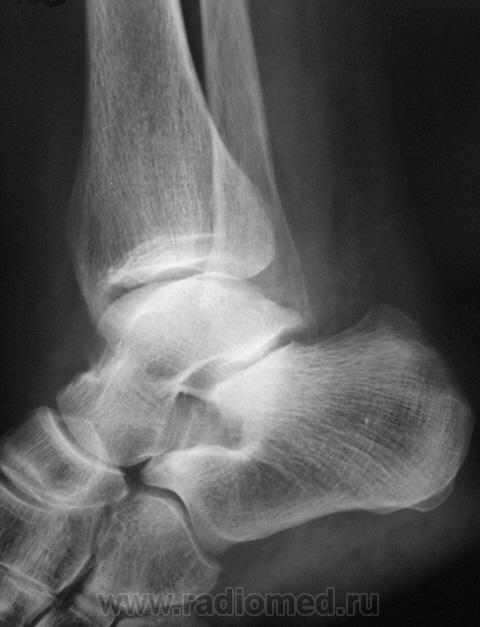

перелом наружной лодыжки без смещения отломков.

Похоже на перелом лодыжки, есть все признаки, но где то подвох, ведь Валентин Львович банальный перелом лодыжки, которые десятки в день проходят, на сайт бы не выставил

Ну, что Вы? Ну какой подвох?